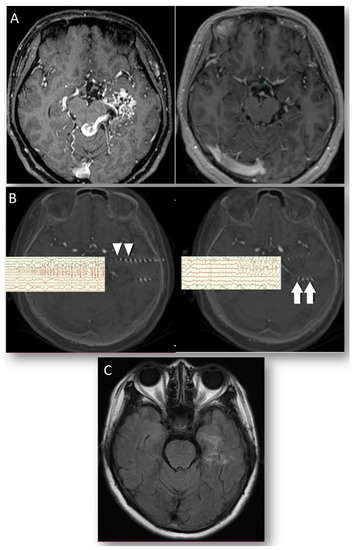

3.3. Case 2. LGS Treated with Anterior CC

| 2 | Male | 9 | Lennox Gastaut syndrome | Anterior callosotomy | Corpus callosum | 2 | 1867.87 | 1841 (1.4%) | 1 | 4 | none | 4 |